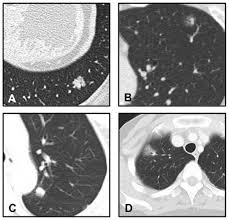

Sometimes there is only a single metastasis in one lung. If the cancer has reached these lymph nodes, cancer cells may have spread to other lymph nodes and other parts, such as the lungs, liver, and bones. When uterine cancer spreads ( metastasizes) outside the uterus, cancer cadres are often may be in nearby lymph nodes, nerves, or blood vessels. Sometimes there are many metastases in one or both lungs. Cancer cells that have entered the bloodstream can get stuck in the small blood vessels (capillaries) of the lungs. About half of people with cancer develop a pleural effusion. It must be realized the progression of uterine cancer. Breast cancer tends to metastasize preferentially to the bone, lung, liver, spine and larger bones, brain, in that order of prevalence. Some general symptoms that breast cancer may have spread include: This is not secondary breast cancer. Download a quick guide to the signs and symptoms of secondary breast cancer. Some common signs of metastatic cancer include: It wouldn't be called lung cancer because if you were to look at a metastasic tumor under a microscope, you would see that they are cancerous breast cells, not cancerous lung cells.

When cancer grows in the pleural space, it causes a malignant pleural effusion. Most lung metastases develop near the edges of the lungs and in the lower lobes. This is because the blood from most parts of the body flows back to the heart and then to the lungs. Download a quick guide to the signs and symptoms of secondary breast cancer. Your doctor will talk with you about which (if any) of these tests you will need. When breast cancer spreads beyond the breast, one of the most common places it goes is the bones (it may also spread to the lungs, liver, or brain). However each case of cancer is not the same (unique). This is not secondary breast cancer. Not all women with breast cancer need these tests. When cancer spreads to a new area, it's still named after the part of the body where it started. Breast cancer tends to metastasize preferentially to the bone, lung, liver, spine and larger bones, brain, in that order of prevalence. This is because the cancer has spread to other organs and is affecting other body systems, as well as. This condition is a sign that the cancer has spread, or metastasized, to other areas of the body.